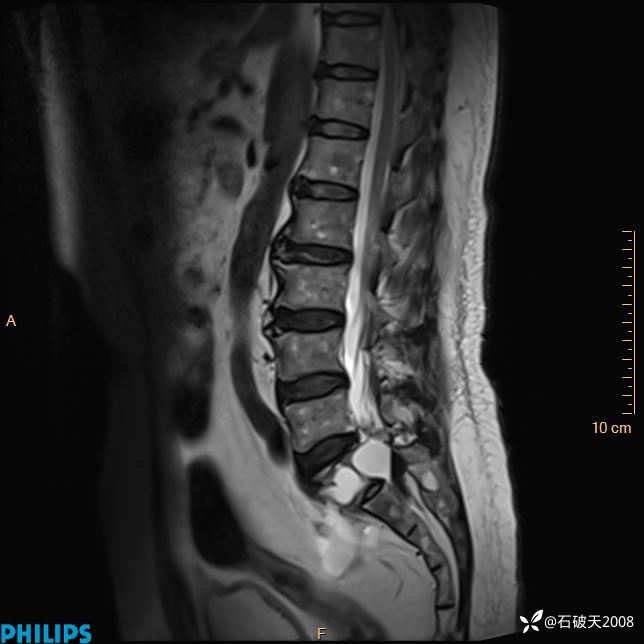

2023年3月份MRI影像

T2矢状位压脂